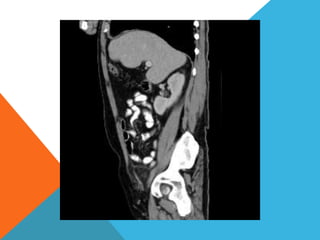

El paciente presentó síntomas de sangrado digestivo y pérdida de peso. Exámenes revelaron gastritis crónica asociada a H. pylori. Un tumor fue descubierto en una colonoscopia normal. La cirugía removió un tumor fibroide solitario, una rara neoplasia mesenquimal que usualmente crece lento y tiene bajo potencial de malignidad. El pronóstico después de la remoción quirúrgica es generalmente bueno.